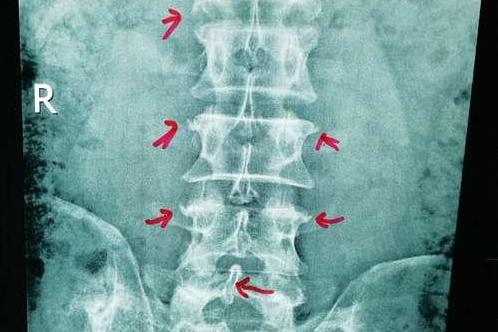

腰椎骨刺是脊柱退变性疾病的一种表现,常伴随腰椎间盘突出等病变,针对这一病症,治疗方法需根据病情轻重逐步深入,主要包括生活调整、药物治疗、物理治疗等。